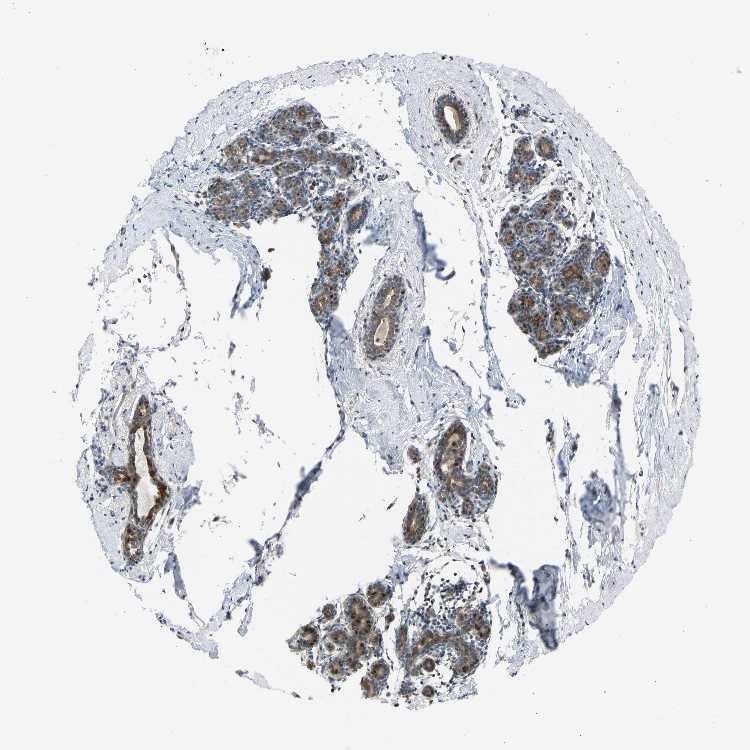

BREAST - Antibody stainingi

Antibody staining in the annotated cell types in the current human tissue is reported as not detected, low, medium, or high, based on conventional immunohistochemistry profiling in selected tissues. This score is based on the combination of the staining intensity and fraction of stained cells.

Each image is clickable and will lead to virtual microscopy that enables deeper exploration of all samples and also displays staining intensity scores, fraction scores and subcellular localization as well as patient and tissue information for each sample.

Antibody HPA020080Antibody HPA020299

Adipocytes Not detectedNot detected

Glandular cells MediumHigh

Myoepithelial cells MediumMedium